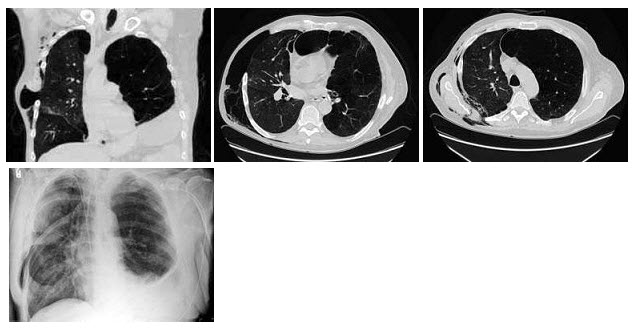

男,68岁,胸闷、气逼1年余,加重1周,右胸有手术史,结合CT图像,最可能的诊断是()A: 右侧气胸并皮下气肿、左侧肺气肿B: 右侧气胸并皮下气肿、左侧肺不张C: 双侧肺气肿D: 右侧气胸并皮下气肿E: 右侧肺间质病变、左侧肺气肿

- A: 右侧气胸并皮下气肿、左侧肺气肿

- B: 右侧气胸并皮下气肿、左侧肺不张

- C: 双侧肺气肿

- D: 右侧气胸并皮下气肿

- E: 右侧肺间质病变、左侧肺气肿